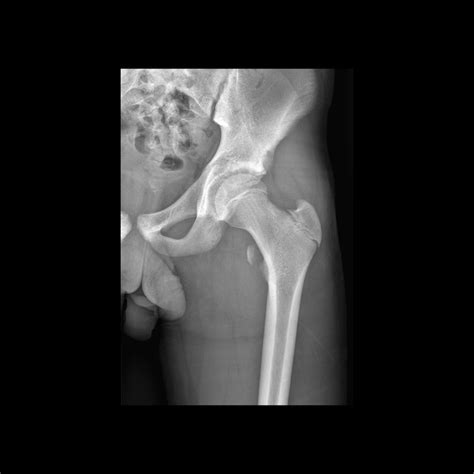

Avulsion Fractures

Avulsion fracture of the lesser trochanter occur when the iliopsoas sinew pulls off from the bone, taking a sherd of the less trochanter with it. These injuries are typically seen in adolescents and young adults who enter in sports that involve sudden, forceful hip flexure, such as soccer, basketball, and track and field. Avulsion fractures can cause hurting, swell, and trouble with hip flexion and weight-bearing action.

Case Study 1: Avulsion Fracture in a Soccer Player

A 16-year-old male soccer musician represent with sudden onset of inguen hurting during a game. He reported feel a "pop" in his groin area and was ineffectual to proceed acting. An X-ray revealed an avulsion fracture of the lesser trochanter. The instrumentalist was treated guardedly with rest, ice, compression, altitude (RICE), and physical therapy. He gradually return to soccer after six workweek and made a total retrieval.